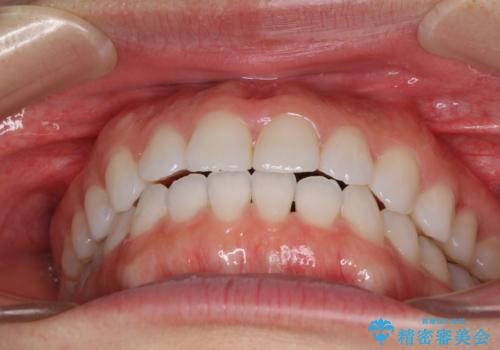

反対咬合を治したい インビザラインによる矯正治療

インビザラインによる反対咬合の改善は、上の歯が下の歯を乗り越えていく期間に咬み合わせが非常に不安定となり、治療が長期化することがあります。

こちらの患者様も、一時的に前歯でしか咬めない時期がありましたが、比較的早く咬み合わせが安定し、1年ほどで治療を終えることができました。